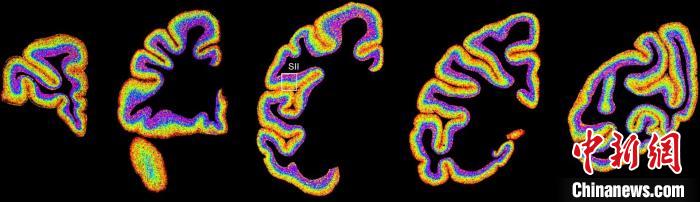

圖為不同類型細(xì)胞在獼猴大腦上的分布切片。 中國(guó)科學(xué)院腦科學(xué)與智能技術(shù)卓越創(chuàng)新中心 供圖

李澄宇說(shuō),科研人員做的事情好似“查戶口”,也就是搞明白猴腦里有哪些細(xì)胞、這些細(xì)胞在哪些位置。搞明白這些就形成了一個(gè)大的數(shù)據(jù)集,科研團(tuán)隊(duì)挖掘這個(gè)數(shù)據(jù)集,發(fā)現(xiàn)了很多有意思的現(xiàn)象:比如,興奮性神經(jīng)元、抑制性神經(jīng)元以及非神經(jīng)元在大腦皮層中的分布呈現(xiàn)明顯的特異性,也就是不同細(xì)胞“住”哪,有一定規(guī)律。